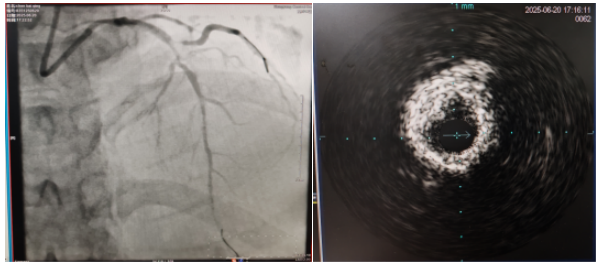

術(shù)中,趙慶禧主任醫(yī)師、雷剛副主任醫(yī)師運(yùn)用IVUS血管內(nèi)超聲技術(shù)評(píng)估,發(fā)現(xiàn)患者前降支、對(duì)角支0.1.1型真性分叉病變,前降支近中段嚴(yán)重鈣化、成角并99%狹窄,對(duì)角支近段嚴(yán)重鈣化并99%狹窄,傳統(tǒng)冠狀動(dòng)脈旋磨術(shù)容易引起冠狀動(dòng)脈穿孔,決定采用沖擊波球囊技術(shù)即血管內(nèi)沖擊波鈣化碎裂術(shù)對(duì)患者嚴(yán)重鈣化的血管進(jìn)行介入治療。通過球囊低壓擴(kuò)張,向血管病變處發(fā)射非聚焦、低能量、脈沖式的沖擊波,對(duì)前降支及對(duì)角支進(jìn)行了連續(xù)5個(gè)周期沖擊波脈沖治療,安全地碎裂淺、深層鈣化,原本看似堅(jiān)不可摧的環(huán)形鈣化區(qū)逐漸顯現(xiàn)出了裂痕,多處關(guān)鍵位置發(fā)生了斷裂,充分預(yù)處理后于前降支近中段串聯(lián)植入支架3枚,對(duì)角支植入藥物球囊,術(shù)后造影見血管病變處狹窄完全消失,支架膨脹完全,貼壁良好,各項(xiàng)生命體征平穩(wěn),手術(shù)非常成功,患者返回心血管內(nèi)科病房繼續(xù)治療,并于4天后順利出院。